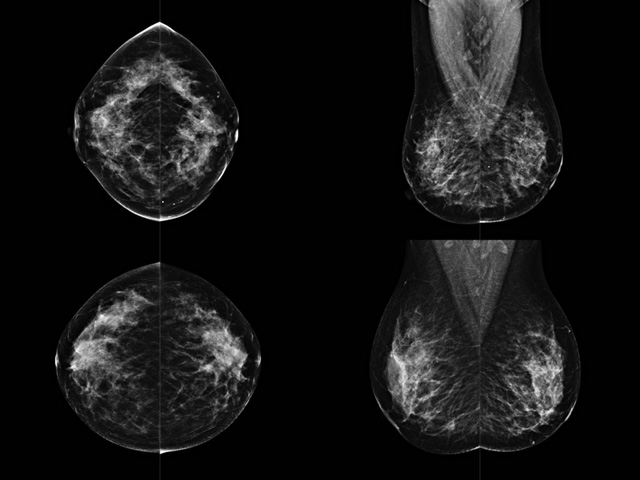

乳腺DR成像設(shè)備中非晶硅跟非晶硒兩種平板探測器。更要提供優(yōu)質(zhì)的圖像質(zhì)量乳腺的組織結(jié)構(gòu)與厚度各不相同,減少重拍率輻射劑量,,乳腺的主要構(gòu)成組織均為軟組織結(jié)構(gòu),組織之間密度十分相似,缺乏天然對比度。選擇軟X線攝影技術(shù)獲得良好對比度的乳腺結(jié)構(gòu)影像。增加各組織對X線的吸收差異。乳腺攝影測和分類,平板探測器的像素尺寸范圍應(yīng)在50到100μm之間。特別是微鈣化灶可以小到100到200μm,平板探測器都必極小微鈣化灶進(jìn)行成像。

乳腺DR是利用X光來做檢查,在一瞬間將被檢測到的位置投影出來,因?yàn)槭撬查g的輻射,所以只需要0.5秒的時間。因此對病人的輻射很低,大約是0.023mSv,比國家的標(biāo)準(zhǔn)要低得多。DR系統(tǒng)由 X線、發(fā)生裝置、直接轉(zhuǎn)換平板探測器、系統(tǒng)控制器、影像監(jiān)視器、影像處理工作站等組成。能檢查胸腔積液、肺結(jié)核、大葉性肺炎、肋骨骨折等。心室增大、主動脈擴(kuò)張、主動脈瘤等心臟病。腹部病變,如腸梗阻、腸穿孔等,DR上可見液氣平面、膈下游離氣腫。DR表現(xiàn)不正常,要結(jié)合臨床表現(xiàn)、體征、癥狀等綜合分析,結(jié)合CT、彩超、血液分析等,才能作出正確的判斷。